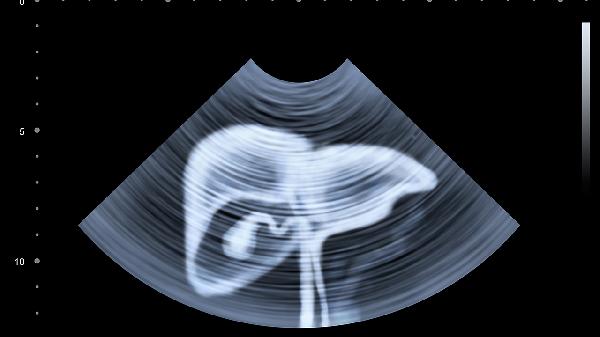

每年至少做一次肝脏超声和肝功能检查,40岁以上建议每半年一次。